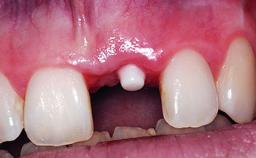

A 49-year-old female patient was referred for implant therapy to replace the upper right central incisor (tooth 11). The tooth had been assessed by an endodontist who diagnosed a vertical fracture of the root. The tooth had a hopeless prognosis and needed to be extracted. The patient was healthy and was not taking any medications. She was allergic to penicillin. The patient had high esthetic demands but her expectations were realistic. The extraoral examination revealed no facial asymmetries. The right temporomandibular joint demonstrated an opening click but was otherwise asymptomatic. The lip line was high with a significant gingival display.

| Placement Protocol | Early or late implant placement |